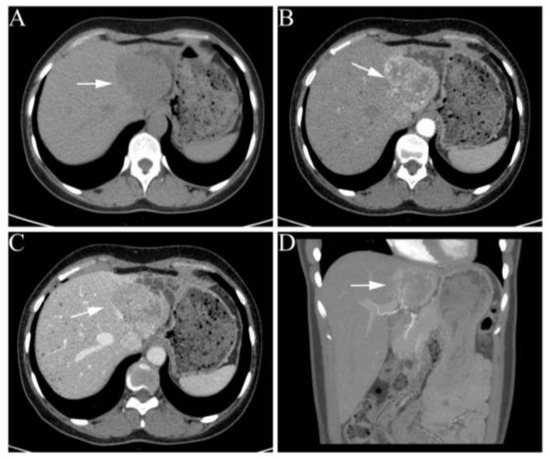

A 34-year-old female patient presented to our hospital with a solitary lesion in her left lateral lobe (Figure 1A), who suffered symptoms of hypertension, palpitations, and dizziness since becoming pregnant. An ultrasound from the community hospital showed a 5.0 cm mass in the left lateral lobe. There was no serologic evidence of hepatitis B or C virus infection. Additionally, the blood tests showed excess catecholamines but normal alpha-fetoprotein (AFP) and vitamin K absence/antagonist-II (PIVKA-II) (Table 1), which were differentiated from typical hepatocellular carcinoma.

Figure 1.

Abdominal contrast-enhanced CT images of the liver. (A) Non-enhanced scan shows a hypodense, well-marginated mass, measuring 6.5 × 5.7 cm. (B–D) A round inhomogeneous enhancement lesion in the early arterial phase and slight washout in the portal phase. White arrows indicate the liver lesion.

Abdominal enhanced computed tomography further revealed an irregularly shaped and poorly circumscribed lesion, measuring 6.5 × 5.7 cm in segments II and III of the liver with mild dilatation of intrahepatic bile duct. The single liver lesion was hypervascular and markedly enhanced in the early arterial phase, with slight washout in the portal phase (Figure 1B–D). The patient had no family history of related tumors. Her blood pressure measurements remained above 140/90 mmHg despite the use of beta-blockers, calcium-channel blockers, and diuretics in combination prior to admission. On admission, her blood pressure was 186/118 mmHg, and her heart rate was 84 beats per minute.